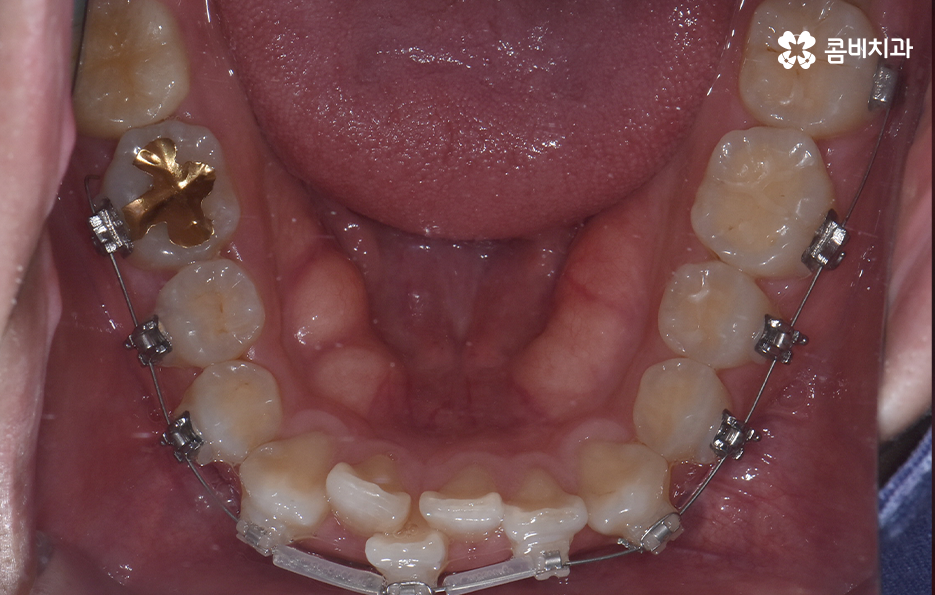

하지만 위에 보시는 환자분의 사례는 윗니와 아랫니의 교합을 고려하고 얼굴형, 골격 등을 고려했을 때도 아랫니만 교정이 가능했던 사례인데 일반적으로 윗니가 아랫니를 살짝 덮고 있어야 하는데 아랫니의 앞니 부분이 유독 안으로 들어와 있었기 때문에 아랫니교정 만으로도 치아교정이 가능했던 사례라고 보시면 좋을 거예요

위 환자분의 사례로 보면 아랫니 중에 하나가 유독 앞으로 튀어나와 있고 나머지 치아는 안으로 들어가 있기 때문에 교합으로 따져볼 때는 아랫니를 전체적으로 앞으로 이동시켜야 했기 때문에 비발치로도 충분히 교정이 가능했고 아랫니교정 만으로도 치료가 가능했어요